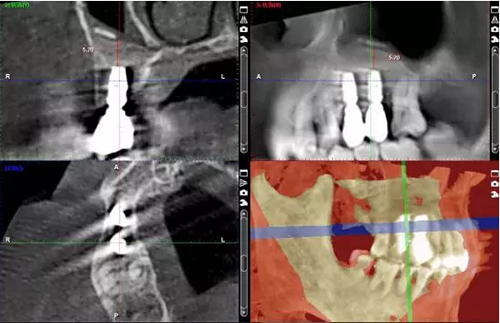

術(shù)后當(dāng)天 術(shù)后7個月

術(shù)后8個月 術(shù)后10個月

術(shù)后13個月

術(shù)后14個月